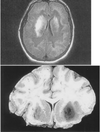

what type of poisoning?

carbon monoxide poisoning- necrosis of globus pallidus and subcortical white matter